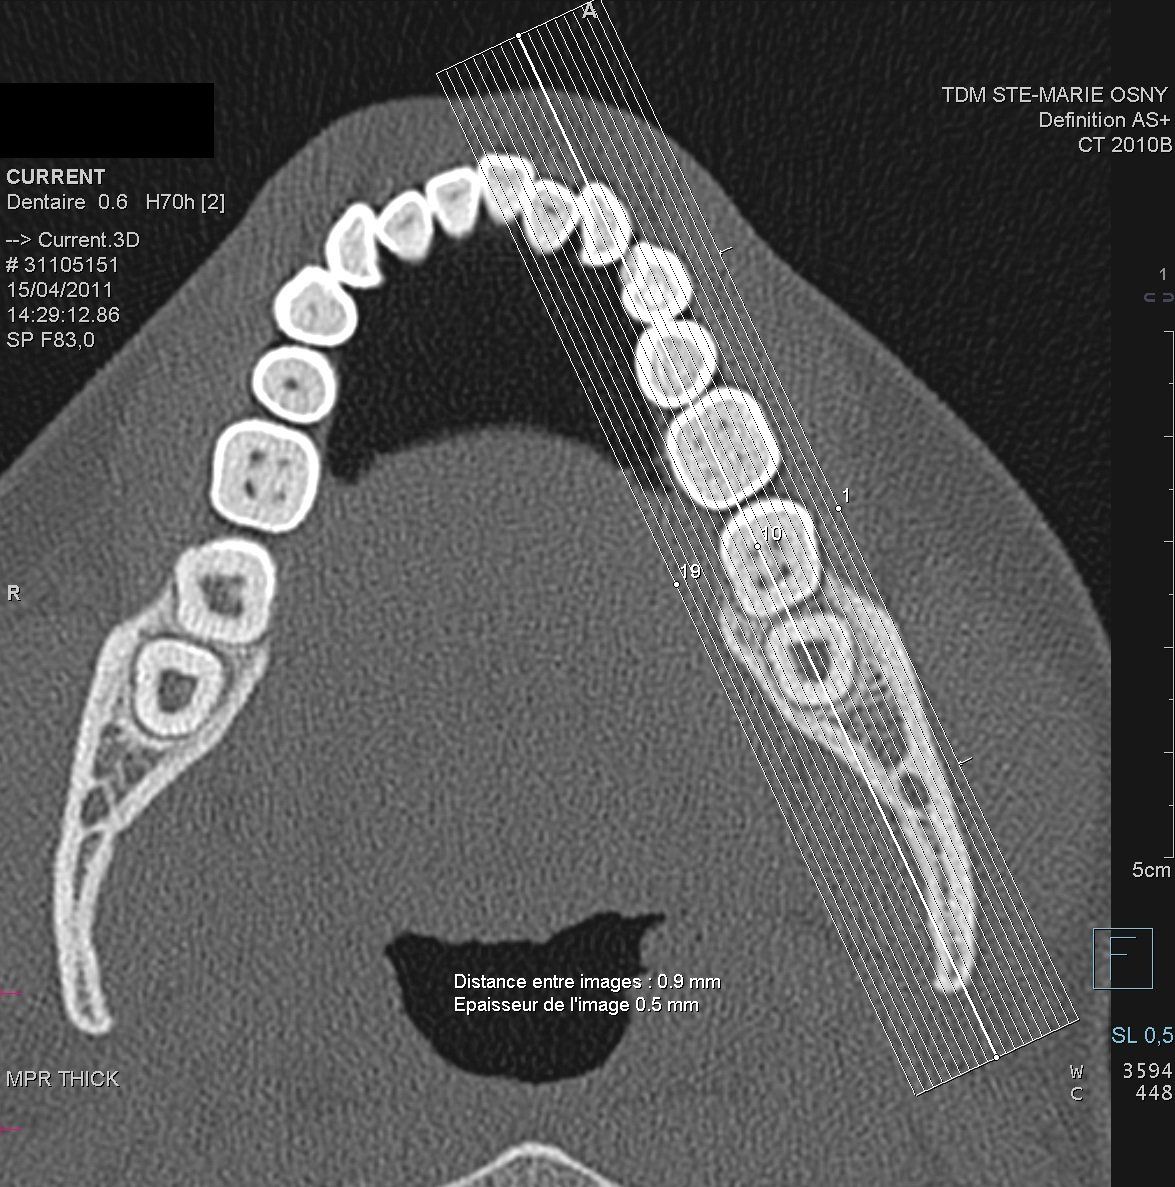

Le principe de la technologie scanner consiste, à l'aide d'un produit de contraste aux rayons x qui sera bu avant l'examen, à détecter les tissus

plus ou moins absorbés par les rayons x selon leur densité. Plusieurs milliers de mesures sont effectuées quasi instantanément et transformées en imagerie

sur l'ordinateur.

Cet examen réalisé par un radiologue avant une intervention chirurgicale permet au praticien d'être guidé et de voir de façon précise d'emplacement de la zone à intervenir.